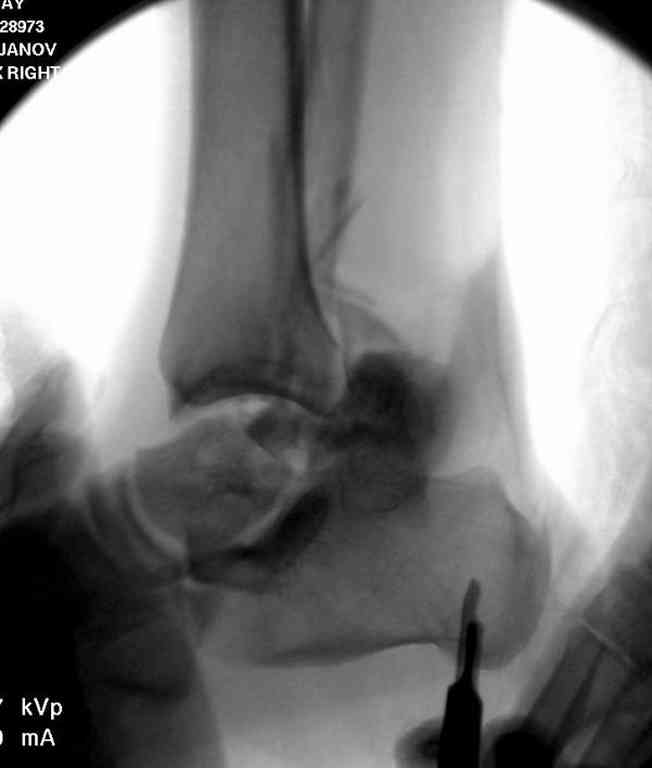

Вчера провели фиксацию.

Из-за многооскольчатости дистальной части малоберцовой, где невозможно было провести фиксацию шурупами, перелом зафиксирован подпирающей пластиной, которая должна служить дополнением отсутствующей дистальной части малоберцовой (lateral cortex substitute).

Для стабильности два шурупа на синдесмоз.

Медиальную рану с приближенными краями продолжаем вакуумировать (KCI). Наружный фиксатор оставлен на пару недель, надеюсь, небольшая рана будет гранулировать и закроется без кожной пластики. Фиксация медиальной ложыжки не планируется.